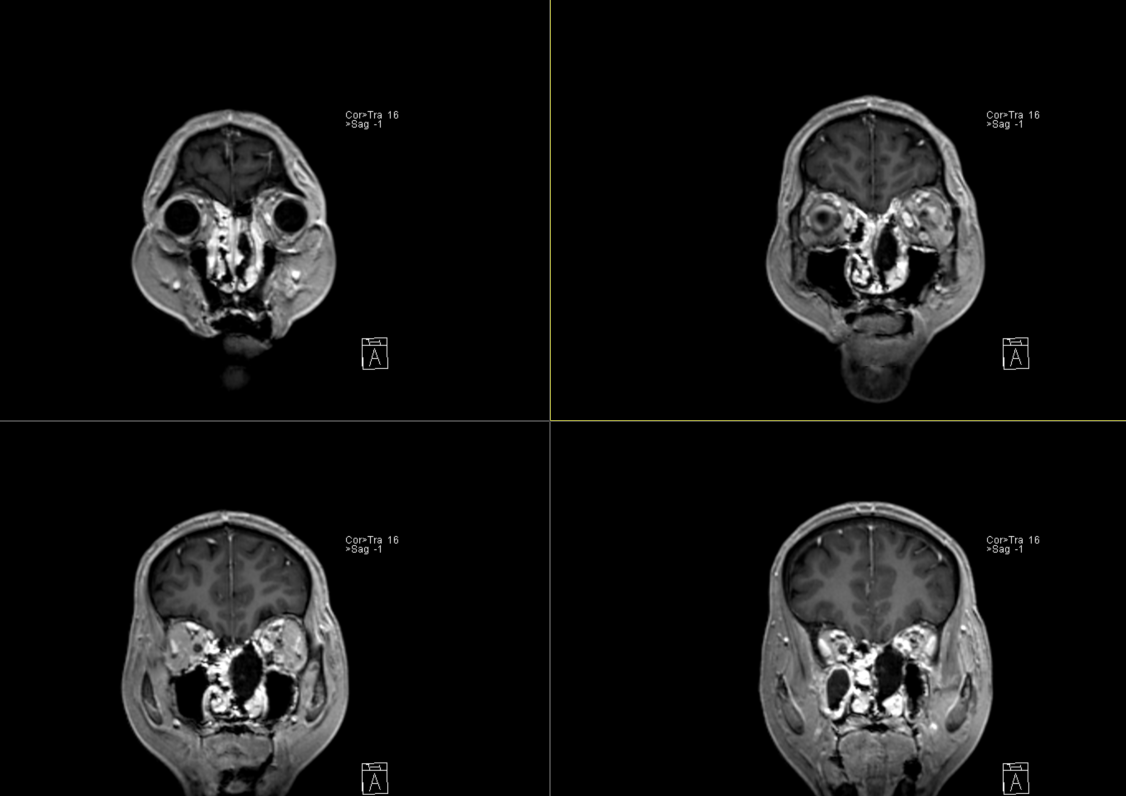

术后影像:

术后影像: